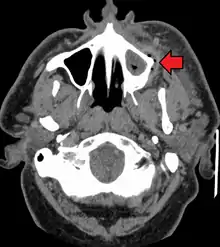

A dental infection resulting in an abscess and inflammation of the maxillary sinus

CT scan showing a large tooth abscess (right in the image) with significant inflammation of fatty tissue under the skin